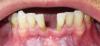

Античелюсть Опубликовано 5 августа, 2011 Поделиться Опубликовано 5 августа, 2011 (изменено) Уважаемые профессионалы, прошу совета. 35 лет полного пофигизма по отношению к собственным зубам за плечами. Щербинка с рождения, но после 16-ти разъехалась до безобразия. Есть и другие проблемы с зубами но пока надо решить проблему с фасадом.Несмотря на то, что было несколько вариантов исправления, вплоть до брекетов, чтобы сдвинуть зубы обратно, пару лет назад сгоряча по совету врача депульпировал четыре передних зуба для постановки моста, то есть с вариантом определился, вернее врач за меня определил после депульпирования отвлекся и зубами не занимался, сейчас продолжил, но несмотря на то, что медицина за это время шагнула вперед даже в такой глухомани, как славный город Волгоград, врач по прежнему советует мост и металлокерамику. Почитав форум - я в сомнении, стоит ли ставить м\керамику, так как доступен оксид циркония и алюминия (клиник, которые используют е-макс не нашел, походив по сайтам местных клиник).Основной довод врача следующий: "зубы у Вас безобразные, мертвые, зачем тратиться на оксид циркония? поберегите свои деньги, поэтому мост и м\кераммика - для Вас предел мечтаний, бла-бла-бла". Действительно ли все так плохо и цельнокерамическая конструкия будет пустой тратой денег? В общем то м\керамика смущает страшилками которые вычитал здесь - синии десны, какие то щели с забившейся пищей, запахи и пр. А может черт на самом деле не так страшен? Тогда сэкономлю и в самом деле. PS может туда посередине имплант воткнуть вобще? PS фото прикладываю, на фото, где "вид ниж челюсти сверху" видно, что десна ушла и передние зубы сильно оголены, от этого или нет, они как будто бы субъективно по ощущениям подвижны, и это беспокоит, можно ли на них мост вообще цеплять. Буду благодарен за любую помощь, очень нужен совет компетентного специалиста, пок родилась мысль походить по разным клиникам поконсультироваться из нескольких мнений выудить лучший вариант избавления от щербинки. Изменено 5 августа, 2011 пользователем Античелюсть Ссылка на комментарий